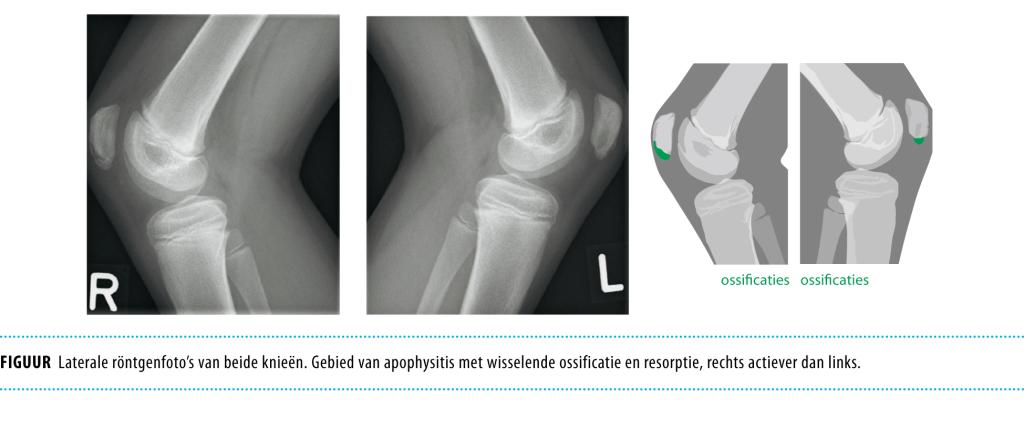

Een 12-jarige jongen presenteerde zich met pijnklachten van de rechter patella na elke voetbalwedstrijd. Anamnestisch was er geen evident trauma. Bij lichamelijk onderzoek was er sprake van een neutrale beenas, symmetrische kniecontouren, geen hydrops, een maximale kniefunctie met niet-afwijkende stabiliteit. Alleen rechts was er lokale drukpijn van de patella-onderpool. Radiologisch onderzoek liet radiolucenties en ossificaties aan de onderpool van beide patellae zien. De diagnose ‘syndroom van Sinding-Larsen-Johansson’ werd gesteld. Deze apofyseletsels komen uitsluitend voor bij actieve jonge sporters van 9-16 jaar. Over de oorzaak bestaan verschillende theorieën, gebaseerd op tractieletsel – recidiverende microtraumata – van de patellapees aan deze…